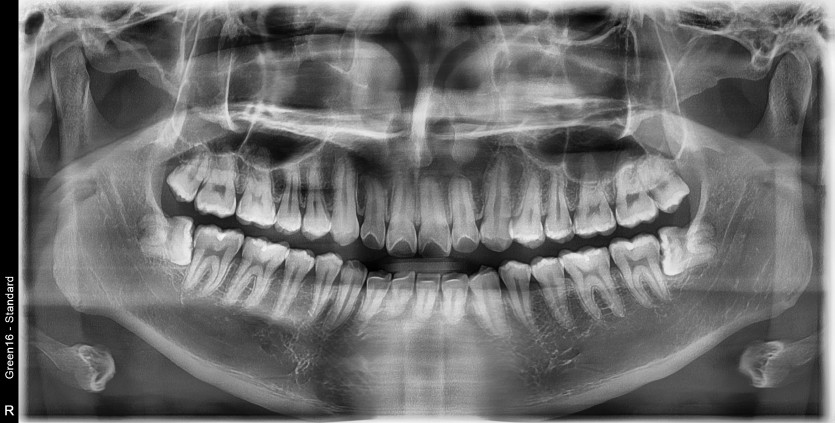

#28,38 사랑니 발치

구강 외과 전문의가 당일 발치하였습니다.